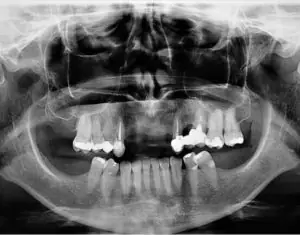

Dental implants can be effective in replacing failed or missing teeth, ensuring aesthetics and saving smiles. But poor oral hygiene, residual cement, smoking, and other